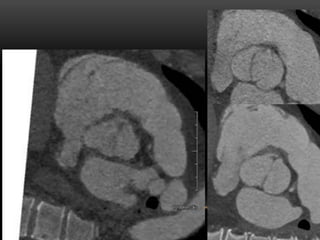

CASE 4

•  32 yr old male

•  Atypical CP, equivocal stress echo

•  Cath: “No vessel coming off R sinus”, concern

for anomalous coronary artery

CASE FOUR

QUADRICUSPID

AORTIC VALVE

QUADRICUSPID AORTIC VALVE

(QAV)

•  Rare, 1/6000 aortic valve surgery patients1

•  M = F, avg. age at Dx ~ 50

•  Classification by size of cusps2

•  Most common: 3 same size + 1 smaller cusp

(type B)

•  Echo: “X”-shaped SAX view

•  CT/MR: confirmatory; perform planimetry and/or

flow measurement3